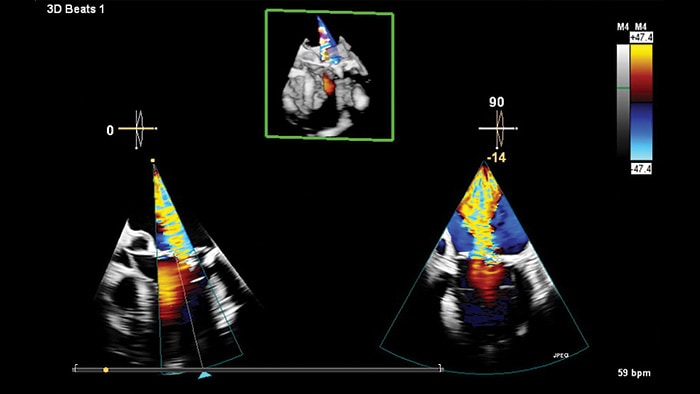

Transcend Plus mejora visiblemente la nitidez, el contraste y el detalle en las imágenes 2D y 3D, con las últimas mejoras aprobadas por la FDA para EPIQ CVx y Affiniti CVx. Estas actualizaciones respaldan una visualización superior de la anatomía y la función cardíacas, lo que permite la confianza en el diagnóstico incluso en los casos más complejos o técnicamente desafiantes. La actualización también presenta la nueva función 2D Auto EF Advanced, que amplía las capacidades de IA para imágenes de contraste, esenciales para evaluar con precisión la función cardíaca.

Transcend Plus permite a los médicos tomar decisiones rápidas y seguras en todos los entornos de atención cardíaca, ya sea en el laboratorio de ecocardiografía, en la sala de intervención o durante las evaluaciones ambulatorias de rutina. Al ofrecer imágenes más nítidas y automatización inteligente, permite una atención más informada, agiliza los flujos de trabajo y ayuda a los proveedores a administrar volúmenes crecientes de pacientes sin comprometer la calidad del diagnóstico o el bienestar del médico. Transcend Plus ofrece tres beneficios principales: calidad de imagen mejorada para una visualización más clara de la anatomía cardíaca y precisión diagnóstica mejorada; integración avanzada de IA, con 26 aplicaciones aprobadas por la FDA que automatizan y aceleran las tareas rutinarias; y conocimientos más rápidos y procesables que reducen las demoras y respaldan las decisiones clínicas oportunas y basadas en evidencia a lo largo del proceso de atención.